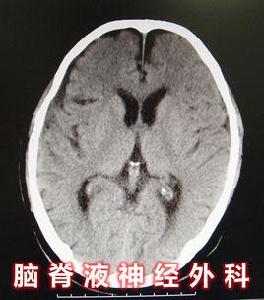

良性高顱壓患者頭顱CT無明顯擴張,腦組織無明顯水腫跡象。行頭顱MRI可排除MS、脫髓鞘等腦組織病變。

3.部分由隱形感染引起的良性高顱壓,雖然CT、MRI顯示腦室系統正常,但存在化學性腦室炎/腦膜炎症狀,需行腦脊液神經外科治療,控制感染,尤其是在中腦-間腦等血-腦屏障缺失部位出現實質性腦損害前開始腦脊液神經外科治療。